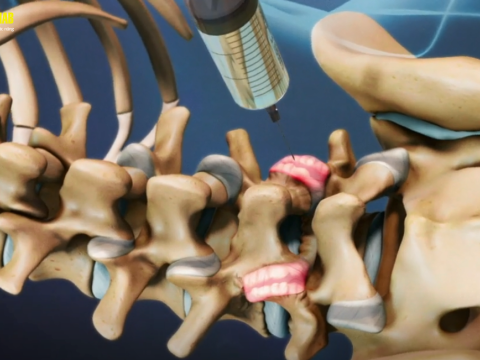

Tiêm cột sống